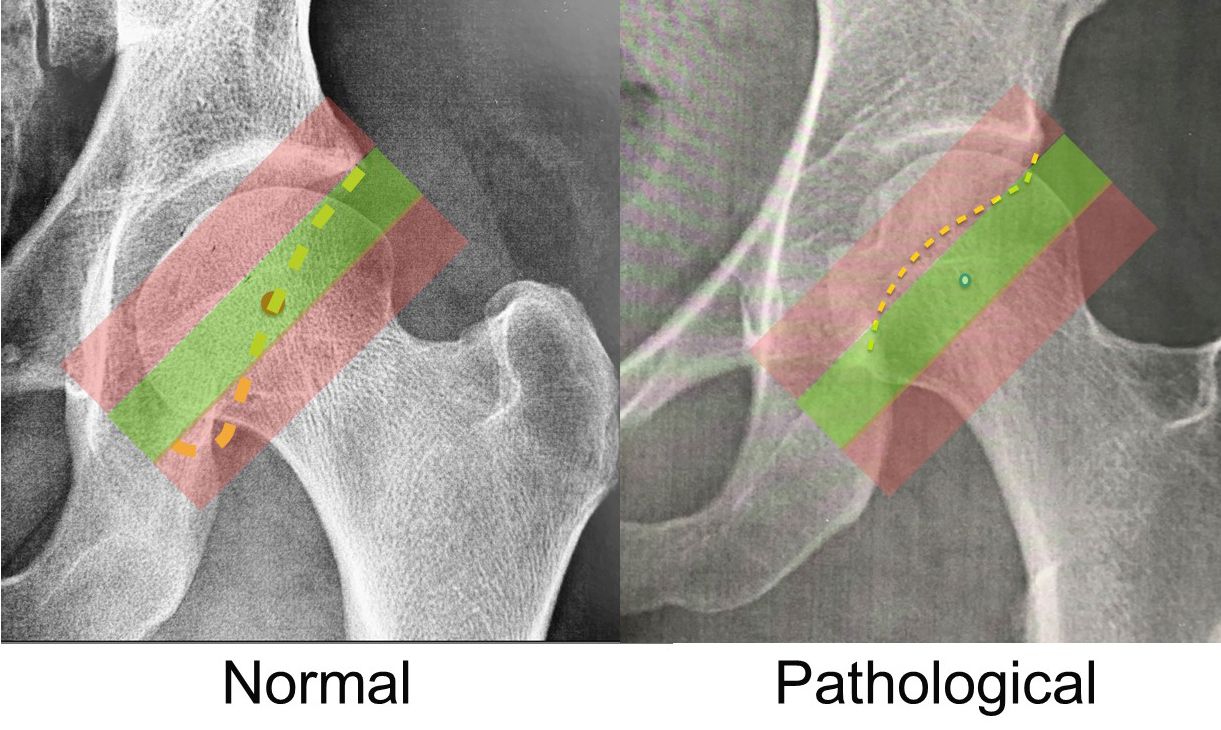

The idea came from the fact that during adolescence, the epiphyseal growth plate of the femur orients itself perpendicularly to the forces applied to it, and thus to the acetabulum. If the hip is unstable and subluxes, the growth plate is no longer parallel to the roof of the acetabulum. A recent study has validated this radiological sign in a group of 150 patients undergoing arthroscopy. The FEAR index was significantly more positive in the unstable hips compared with the stable ones (27). Finally, another excellent sign to be aware of, again described by Marc Safran, is the Cliff Sign (28). An unstable hip will nearly always have a very narrow neck and a head that is no longer a perfect circle, losing some sphericity where it ‘exits’ the acetabulum i.e. around its lateral aspect (Fig. 15). The larger the lateral empty space, the greater the sign.